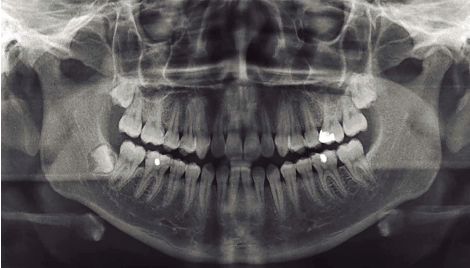

• primera panoramica

primera panoramica

se logra obtener la primera panorámica de toda la boca.